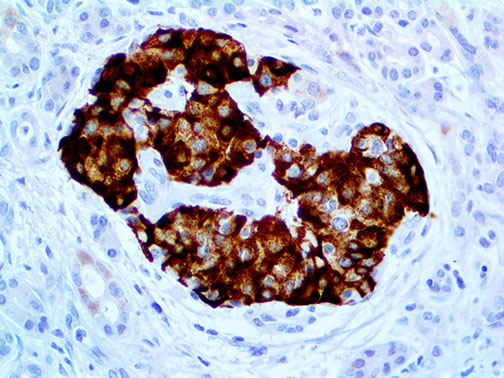

Insulin – MMab

Insulin is a purified immunoglobulin fraction of rabbit antiserum that is filter sterilized and diluted in buffer pH 7.5, containing BSA and sodium azide as a preservative.